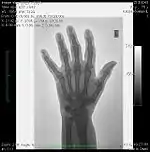

Fig. 6.4: Images of a pelvic phantom demonstrating the dynamic range of CR. The image on the left is taken using 2 mAs and the one on the right using 160 mAs exposure. The major discernible difference is a marked increase in variability of grey levels in the lower exposure image (e.g. see the region shown arrowed, for example).

A second parameter to be derived from the transfer characteristic is the dynamic range, which expresses the range of input signals over which the image receptor is sensitive. In the case of CR, its about four orders of magnitude - see Figure 6.3, which shows its transfer characteristic in comparison to the traditional film/screen technology. The result is that under-exposure and over-exposure of regions traditionally seen radiographs are much less of an issue in clinical imaging. This feature of CR is illustrated by the radiographs in Figure 6.4.

Mottle can typically be seen in radiographic images as minute random fluctuations in the greyness of the anatomical details portrayed - see the images in Figure 6.4, for an example. When these fluctuations are large enough, they may obscure subtle changes in image contrast and render details invisible on the image. We will consider the major source of mottle below.